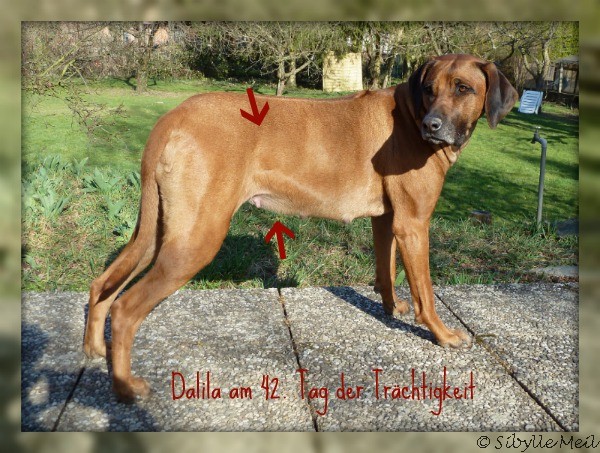

D Litter Diary

Padme s Canine Pregnancy Vlog Day 52 Entry 7 top, My dog is about 51 days pregnant yesterday she started a brown top, LABRADOR RETRIEVER CASSIE 52 DAYS PREGNANT top, How Long Are Dogs Pregnant Labour Gestation Period top, Dog Pregnancy Calendar What To Expect When She s Expecting top, Pregnancy Ultrasound Radiographs Conyers Animal Hospital top, Pregnancy calendar day by day top, Whelping Puppies Unexpected Early Delivery. Raising Puppies top, Week by Week Dog Pregnancy Signs for Proud Puppy Parents top, 38 Days Pregnant Dog 2024 www.gemologytidbits top, Dog Pregnancy Day by Day Timeline Stages and Tests Dog Health Guide top, The Last Week of A Great Dane s Pregnancy Dog Blog It top, My dog is showing all signs of pregnancy but xray showed no top, Canine Pregnancy Calculator and Calendar top, 12 Signs of False Pregnancy in Dogs PetHelpful top, How Long Are Dogs Pregnant Dog Gestation Period top, How Long Are Dogs Pregnant Dog Gestation Period Explained top, Abortion top, D Litter Diary top, Veterinary Sciences Free Full Text Development of Dog Immune top, Diagnosing Treating Canine Dystocia Clinician s Brief top, Canine Pregnancy Scanning West Midlands top, D Litter Diary top, French Bulldog Pregnancy Stages 9 Weeks Of Fun French Bulldog top, Dog Pregnancy Calendar Find Out When Your Canine Is Due To Deliver top, Canine Pregnancy Calendar top, Early Contractions and Labor top, Pregnancy in Dogs Dog News top, Dog Pregnancy Stages Revival Animal Health Learn More top, My dog is showing all signs of pregnancy but xray showed no top, Canine pregnancy diagnosis PPT top, How Long Are Dogs Pregnant Dog Gestation Period top, Welping box is complete 52 days pregnant westbygodvirginiacanecorso gooddogbreeder akccanecorso canecorsopuppies embark top, 5 Ways to Care for a Pregnant Dog wikiHow top, Dog Pregnancy Day by Day Timeline Stages and Tests Dog Health Guide top.

Padme s Canine Pregnancy Vlog Day 52 Entry 7 top, My dog is about 51 days pregnant yesterday she started a brown top, LABRADOR RETRIEVER CASSIE 52 DAYS PREGNANT top, How Long Are Dogs Pregnant Labour Gestation Period top, Dog Pregnancy Calendar What To Expect When She s Expecting top, Pregnancy Ultrasound Radiographs Conyers Animal Hospital top, Pregnancy calendar day by day top, Whelping Puppies Unexpected Early Delivery. Raising Puppies top, Week by Week Dog Pregnancy Signs for Proud Puppy Parents top, 38 Days Pregnant Dog 2024 www.gemologytidbits top, Dog Pregnancy Day by Day Timeline Stages and Tests Dog Health Guide top, The Last Week of A Great Dane s Pregnancy Dog Blog It top, My dog is showing all signs of pregnancy but xray showed no top, Canine Pregnancy Calculator and Calendar top, 12 Signs of False Pregnancy in Dogs PetHelpful top, How Long Are Dogs Pregnant Dog Gestation Period top, How Long Are Dogs Pregnant Dog Gestation Period Explained top, Abortion top, D Litter Diary top, Veterinary Sciences Free Full Text Development of Dog Immune top, Diagnosing Treating Canine Dystocia Clinician s Brief top, Canine Pregnancy Scanning West Midlands top, D Litter Diary top, French Bulldog Pregnancy Stages 9 Weeks Of Fun French Bulldog top, Dog Pregnancy Calendar Find Out When Your Canine Is Due To Deliver top, Canine Pregnancy Calendar top, Early Contractions and Labor top, Pregnancy in Dogs Dog News top, Dog Pregnancy Stages Revival Animal Health Learn More top, My dog is showing all signs of pregnancy but xray showed no top, Canine pregnancy diagnosis PPT top, How Long Are Dogs Pregnant Dog Gestation Period top, Welping box is complete 52 days pregnant westbygodvirginiacanecorso gooddogbreeder akccanecorso canecorsopuppies embark top, 5 Ways to Care for a Pregnant Dog wikiHow top, Dog Pregnancy Day by Day Timeline Stages and Tests Dog Health Guide top.